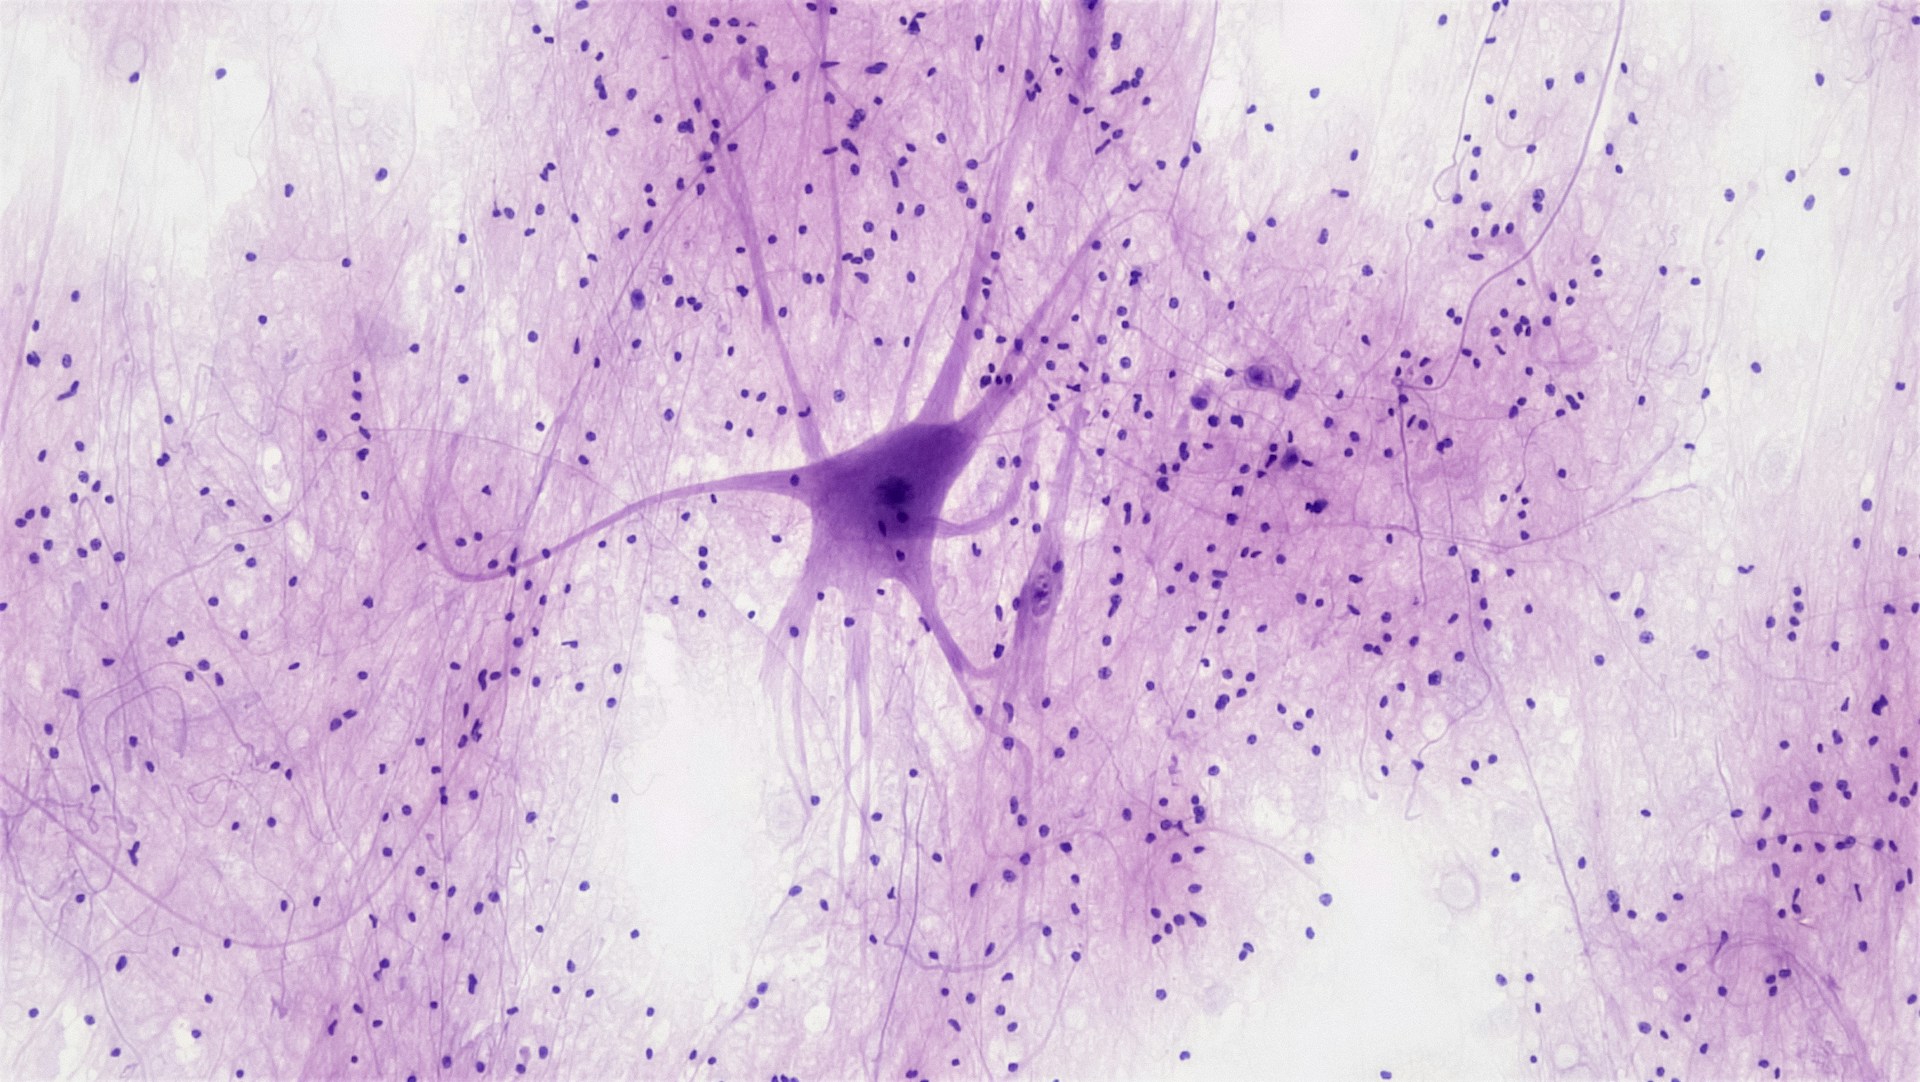

Dans les années 1920, le scientifique Hans Berger (neuropsychiatre & physicien) découvre que notre cerveau produit une activité électrique mesurable en hertz ⚡. Il identifie 5 types d’ondes cérébrales, qui influencent notre état mental et nos émotions.

Les Ondes Cérébrales : Le Pouvoir Caché du Cerveau